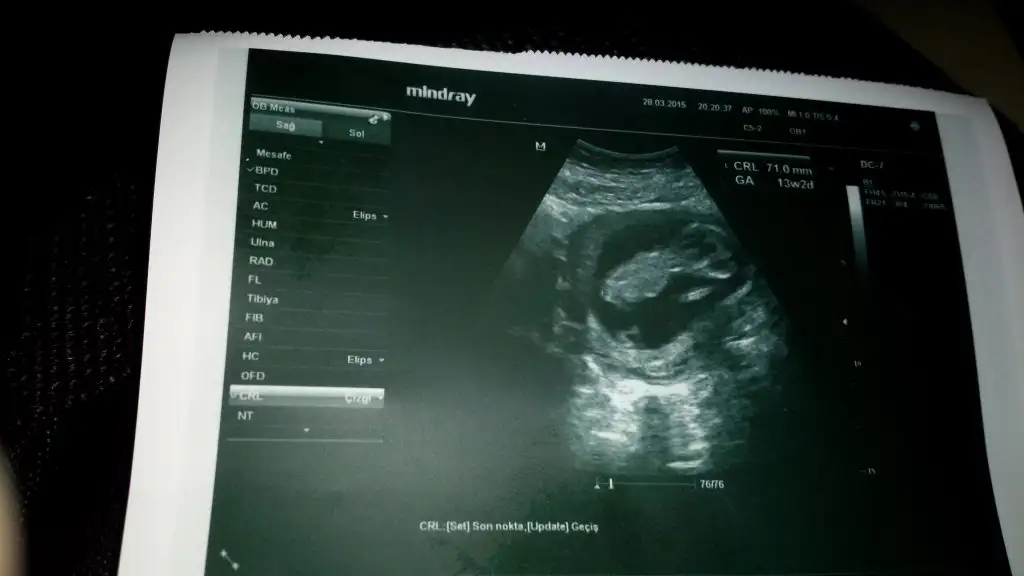

13 haftalık olduk ama bizim minnoş göstermedi doktor haftaya dedi siz ne dersiniz kızlar

Eklentiler

• image.webp

image.webp

15,2 KB · Görüntüleme: 101

bendee çok merak ediyorum meleğimin cinsiyetini :) tahminlerinizi alıyım lütfeen 13 haftalığız

• IMG_20150328_195723.webp

IMG_20150328_195723.webp

18,1 KB · Görüntüleme: 82